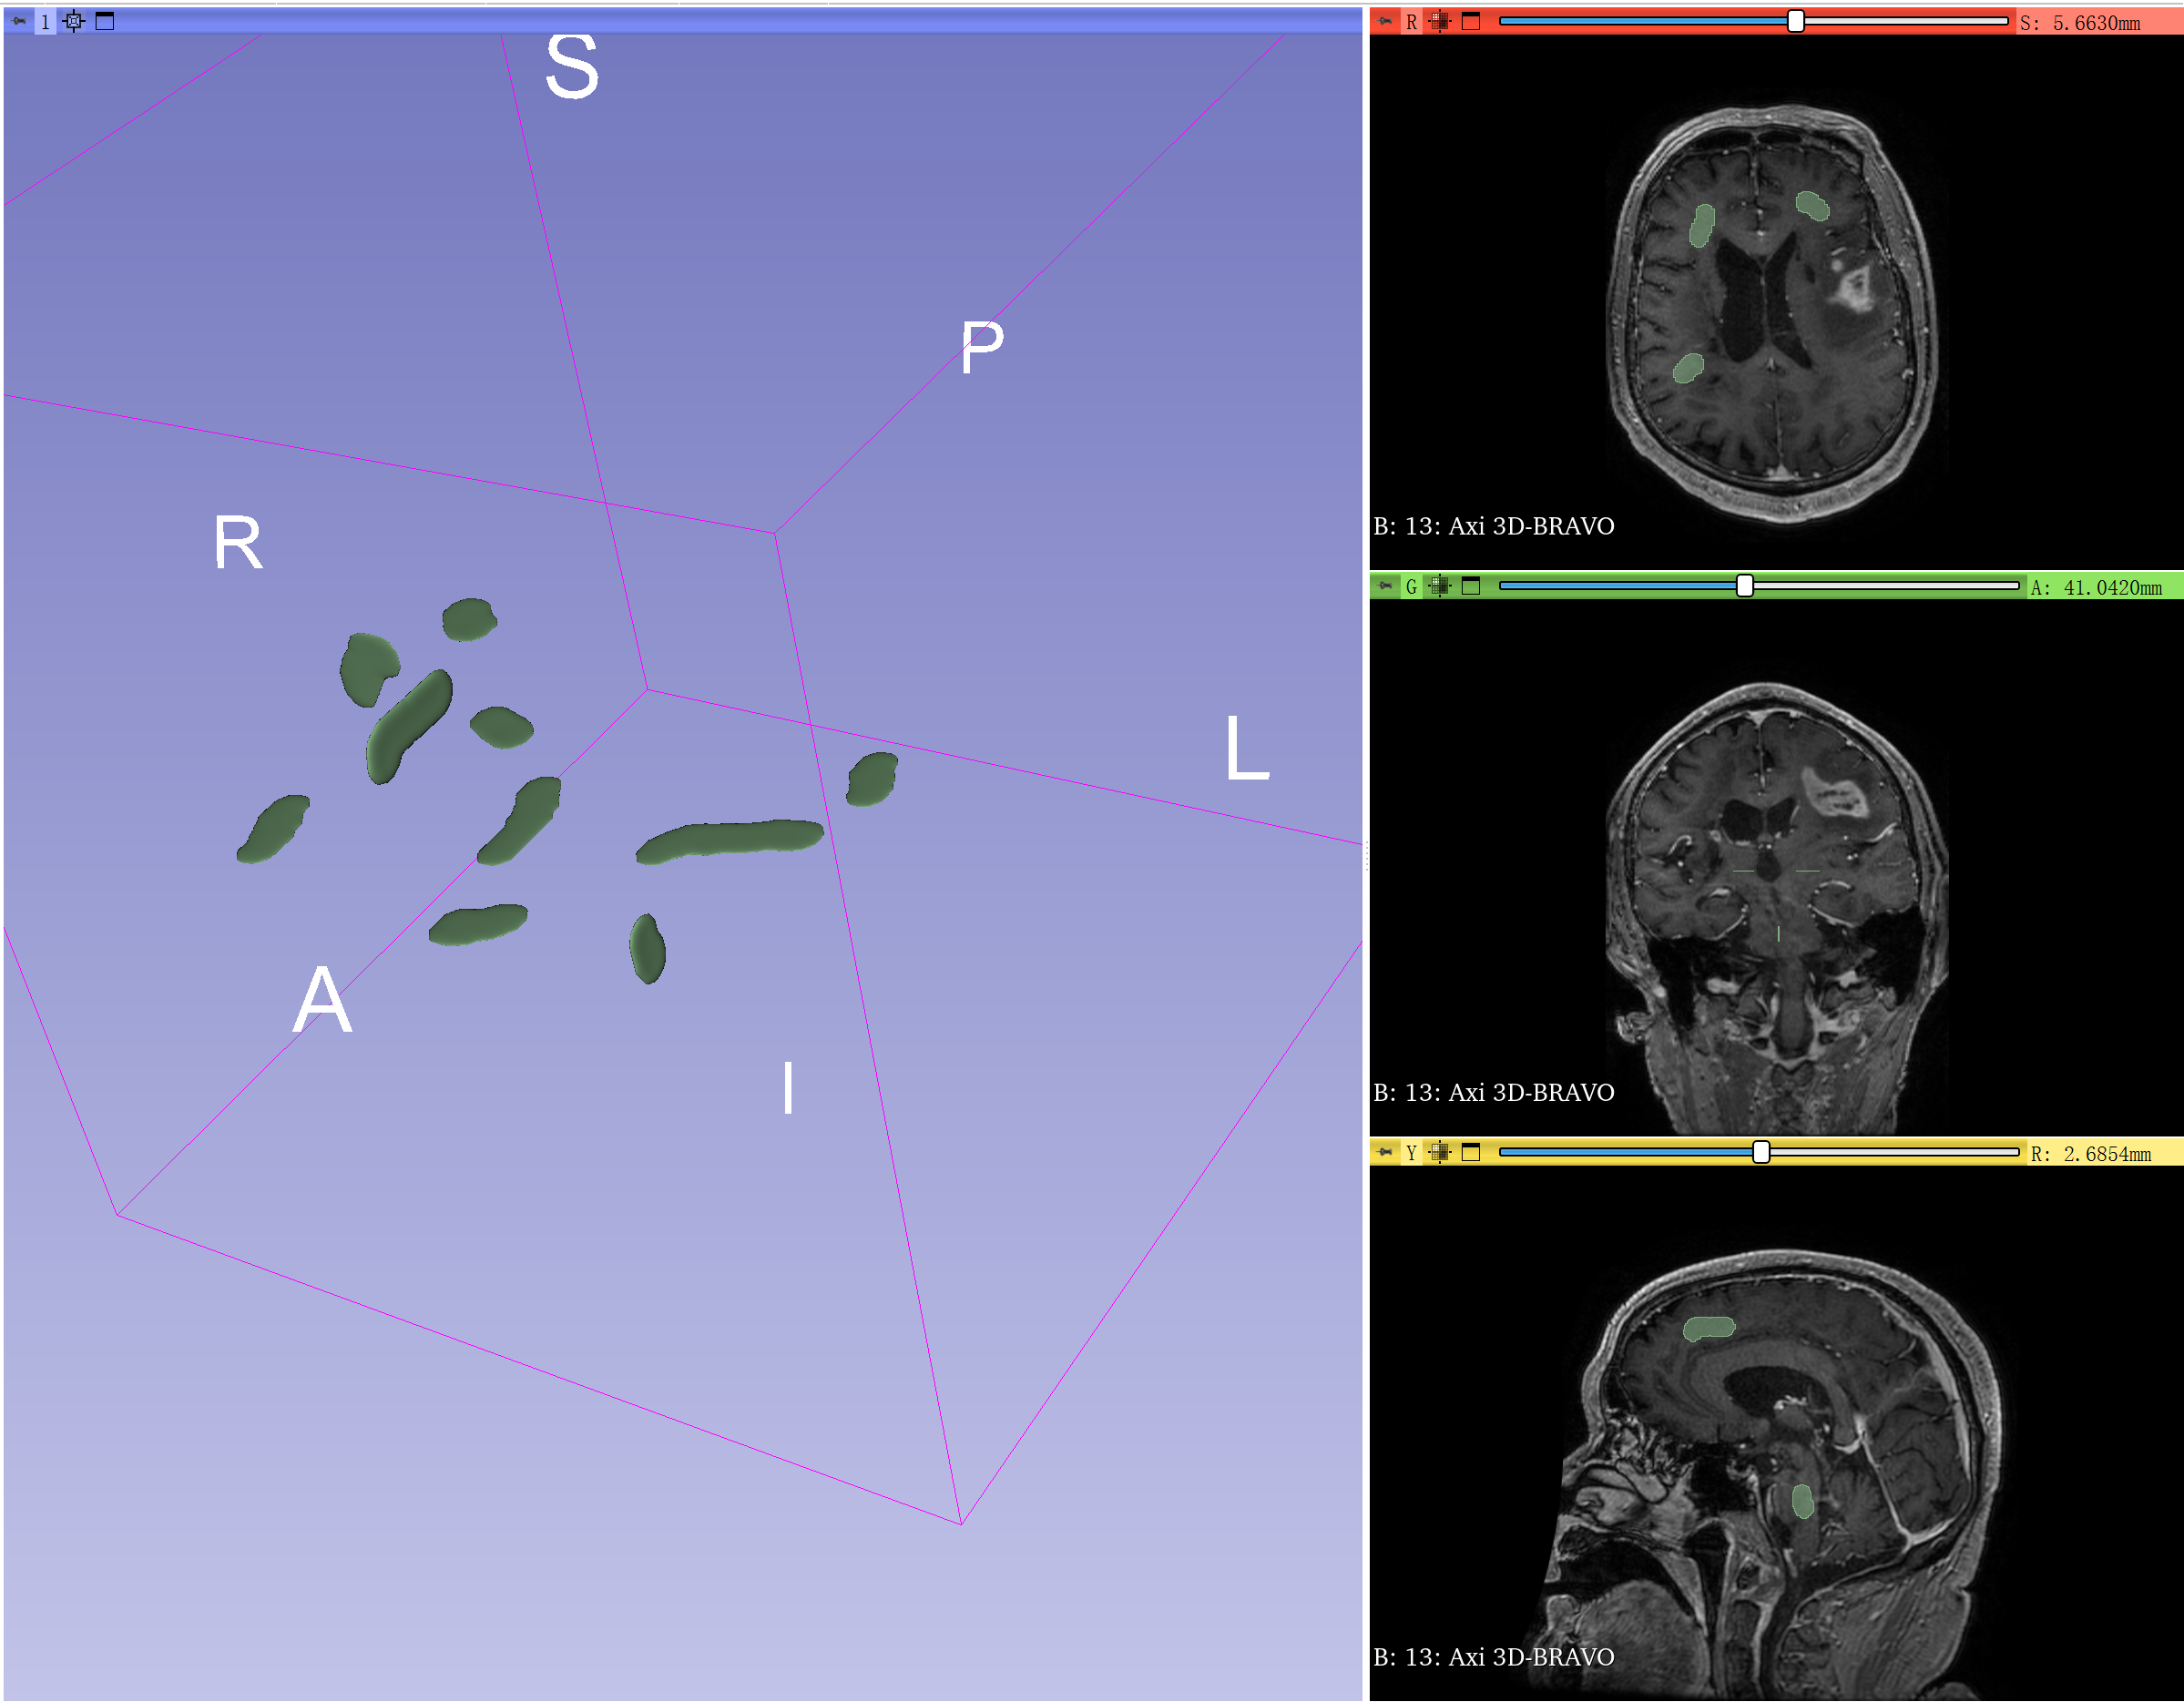

这个操作要用到fast marching工具。

先用paint在脑组织上简单标记,然后运行fast marching。

在MRI上简单paint脑组织。

Initialize后点apply就可以得到下图的结果。